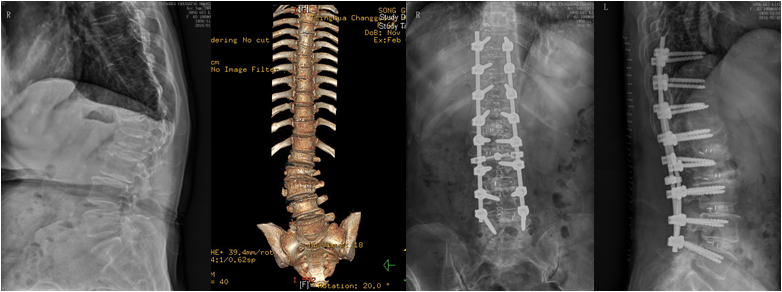

儿童先天性侧弯半椎体伴分隔不全;半椎体切除胸廓成形矫形固定融合

脊柱是人体的中轴骨骼,是身体的支柱,有负重、减震、保护和运动等功能。4位患者中有一位刚满12岁的儿童,儿童期的脊柱侧弯,会随生长发育逐渐进展,青春期时进展速度最快;可能造成严重外形和功能障碍,甚至影响心肺和腹腔内脏功能,而侧弯畸形对孩子的人格心理发育影响更不容小觑。

经完善三维影像学检查,脊柱专业组查房讨论,分别针对4例患者,制订个体化精准减压矫形方案,由肖嵩华教授主刀,宋飞主治医师和脊柱组医师配合,在连续的4个手术日,分别完成胸6半椎体切除胸廓成形矫形固定,腰椎后凸截骨矫形固定融合,退变性侧弯减压矫形固定融合,侧后凸减压截骨矫形融合固定,4台高难度手术均告成功。12岁的男孩是第一个接受手术的患者,男孩父母的心理压力非常大,待医师走出手术室,告知手术成功时,一直坚强的母亲眼泪瞬间流了下来,“这场手术把孩子的命运带回了正常的轨道。”

患者脊柱畸形得到纠正,伴随的椎管狭窄压迫神经等症状也得到彻底根治。困扰患者多年的躯干外形异常和神经功能障碍一去不复返。术后2-3天,4位患者均可下地,“腰杆子直起来了”;“大腿不疼不麻,能正常走路了”;“身高增加了”,脊柱畸形患者术后效果良好,可谓:新年开了个好头。